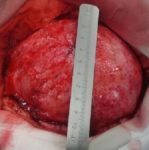

během operace